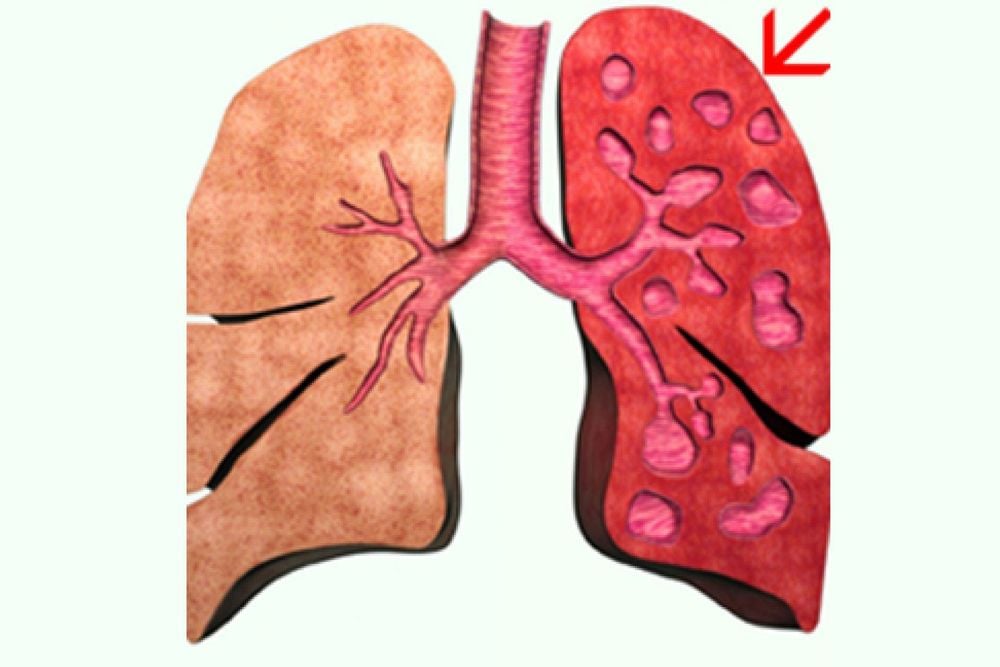

Khi các van này đặt đúng vị trí, không khí sẽ đi ra theo một chiều duy nhất mà không cho phép không khí đi ngược vào lòng phế quản. Lâu dần thùy phổi sẽ xẹp xuống và nhờ đó giảm bớt thể tích phổi, hạn chế tình trạng căng phổi và cải thiện hiệu quả tình trạng hô hấp ở bệnh nhân bị bệnh phổi tắc nghẽn mãn tính có hiện tượng giãn phế nang nghiêm trọng.

- Bệnh nhân bị giãn phế nang không thuần nhất nghiêm trọng, tập trung ở thùy trên của phổi.

- Bệnh nhân bị giãn phế nang thuần nhất.